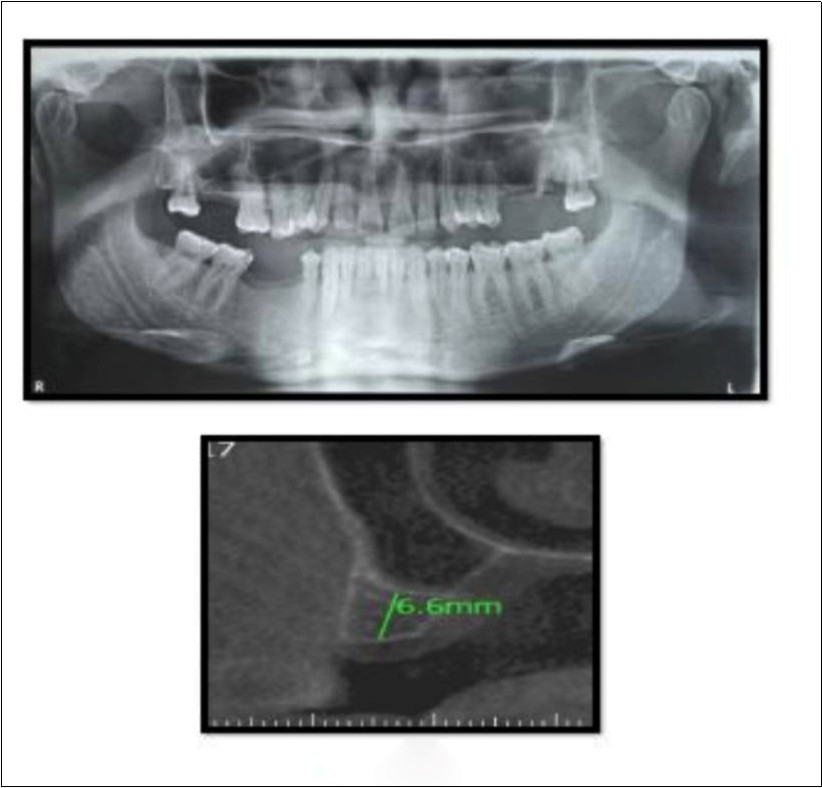

A 45 year old patient with a residual bone height of 6.6 mm in 17 region underwent procedure of indirect sinus elevation using sinus osteotomy in relation to 17 region. Synthetic graft material was dispensed through the crestal osteotomy site to maintain the elevated sinus membrane followed by placement of a dental implant measuring 5 mm x 10 mm under local anesthesia and strict aseptic protocols. The implant was allowed to osseo-integrate for a period of six months during which the patient was followed periodically and was assessed for peri-implantitis, crestal bone loss and mobility. At the end of 6 months, a CBCT scan was advised to evaluate the increase in bone height which was 12mm. (Figure 3, Figure 4)

Figure 3.Pre-operative Orthopantomograph and cross section of CBCT showing residual alveolar bone height

Figure 4.Post-operative Orthopantomograph and cross section of CBCT showing residual alveolar bone height